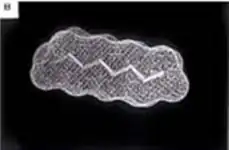

The second image shows experimental results comparing both plasma and tissue levels of gentamicin after an intratracheal (IT) and intravenous (IV) dose of 5 mg/kg in a newborn lamb during gas ventilation. Note that the plasma levels of the IV dose greatly exceed the levels of the IT dose over the 4 hour study period; whereas, the lung tissue levels of gentamicin when delivered by an intratracheal (IT) suspension, uniformly exceed the intravenous (IV) delivery approach after 4 hours. Thus, the IT approach allows more effective delivery of the drug to the target organ while maintaining a safer level systemically. Both images represent the in-vivo time course over 4 hours. Numerous studies have now demonstrated the effectiveness of PFC liquids as a delivery vehicle to the lungs.[35][36][37][38][34][39][33][40][30][41]